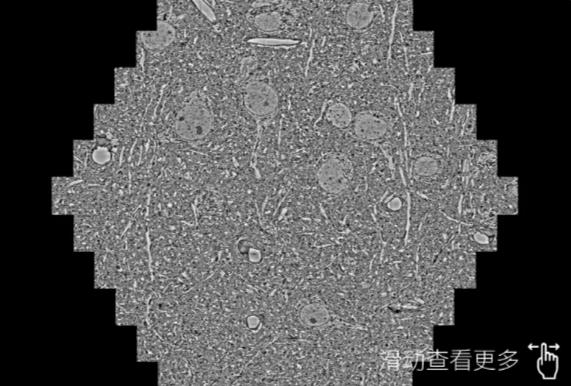

鼠脑切片。左图使用扬州蔡司扬州扫描电镜MultiSEM706对165μmx143pm面积区域成像,耗时仅需1.5秒。右图为鼠脑切片中30μm区域放大效果。样品由芝加哥大学B.Kasthuri提供。

使用蔡司高速扬州扫描电镜MultiSEM对1mm²人脑皮层组织进行高分辨成像,并对其中的各种细胞结构进行三维重构分析。左图展示了2x3mm²组织平面中锥体神经元的三维重构效果。右图显示了局部体积神经元三维重构。图像由哈佛大学chtman实验室提供,渲染图由D. Berger 制作。